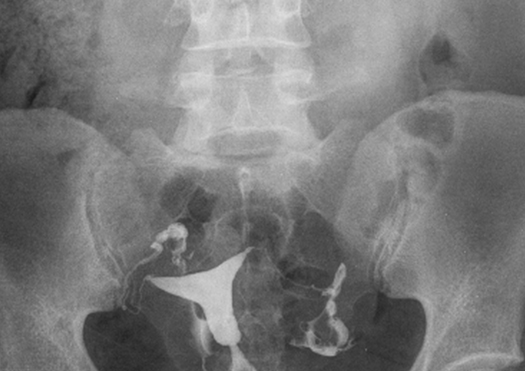

Rayos X

Producen una imagen cuando un haz de rayos X, atraviesa el cuerpo y los diferentes tejidos atenuarán o absorberán cierta cantidad de rayos X, pero habrá algunos que salen del cuerpo y llegan al detector de radiación para generar una imagen.

Post Thumbnail

Fluoroscopia

Técnica dinámica con utilización de Rayos X y medios de contraste para la valoración de distintos sistemas como son Digestivo, Genitourinaria y Vascular principalmente, es una técnica antigua que continúa teniendo gran relevancia en el diagnostico de muchas enfermedades.